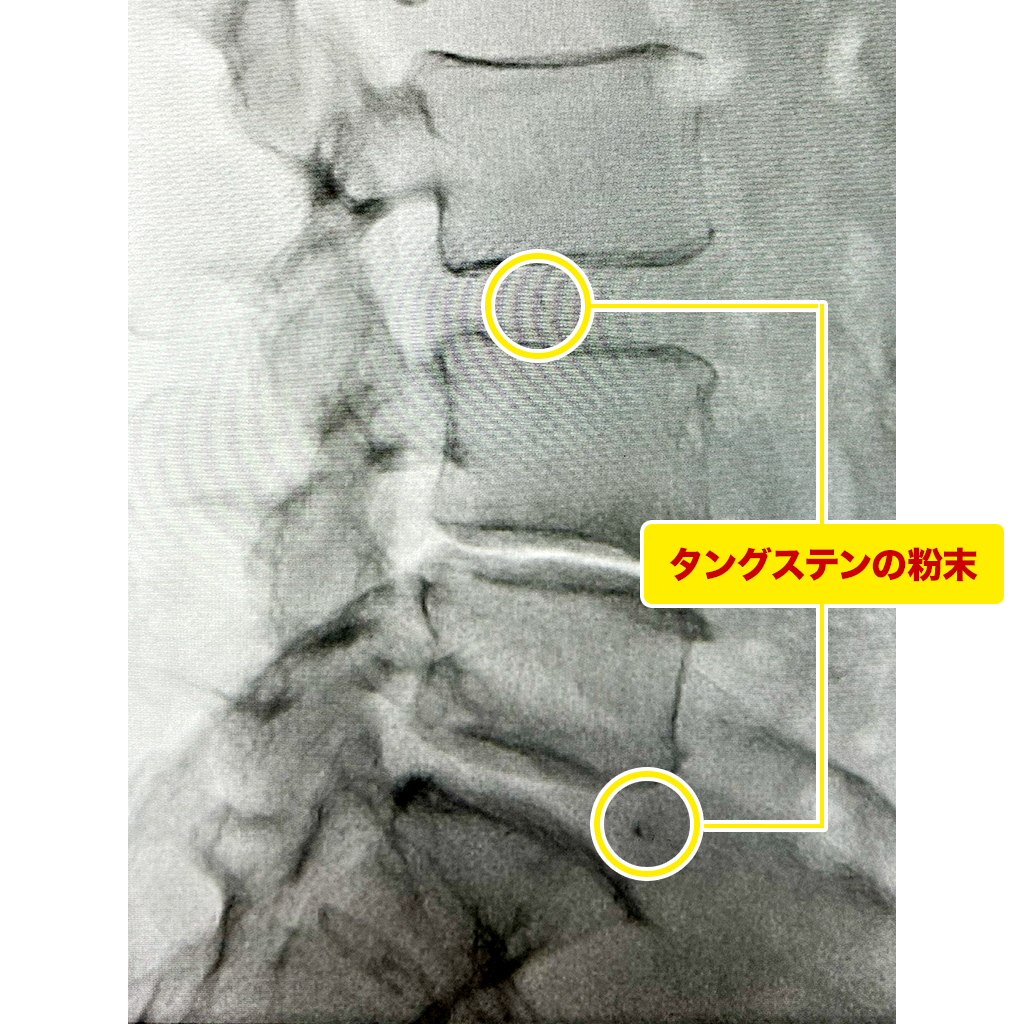

X線検査でL3/4とL5/Sで椎間板内にタングステンの粉末を認めます。L4/5ではハッキリとしません。

セルゲル法はこのような異物を挿入している治療ですので、ディスクシール治療を行うことでどのような合併症や後遺症が起きるか分かりません。異物を椎間板外に押し出してしまい神経を損傷してしまう可能性もあります。患者様には治療のリスクを十分に説明し、同意を得て治療を行いました。

AnnulogramでL2/3を含めて線維輪の損傷を認めました。幸いなことに、L3/4はディスコゲルが注入されていますが、椎間板の変性・損傷はそれほど進行していないように見えます。